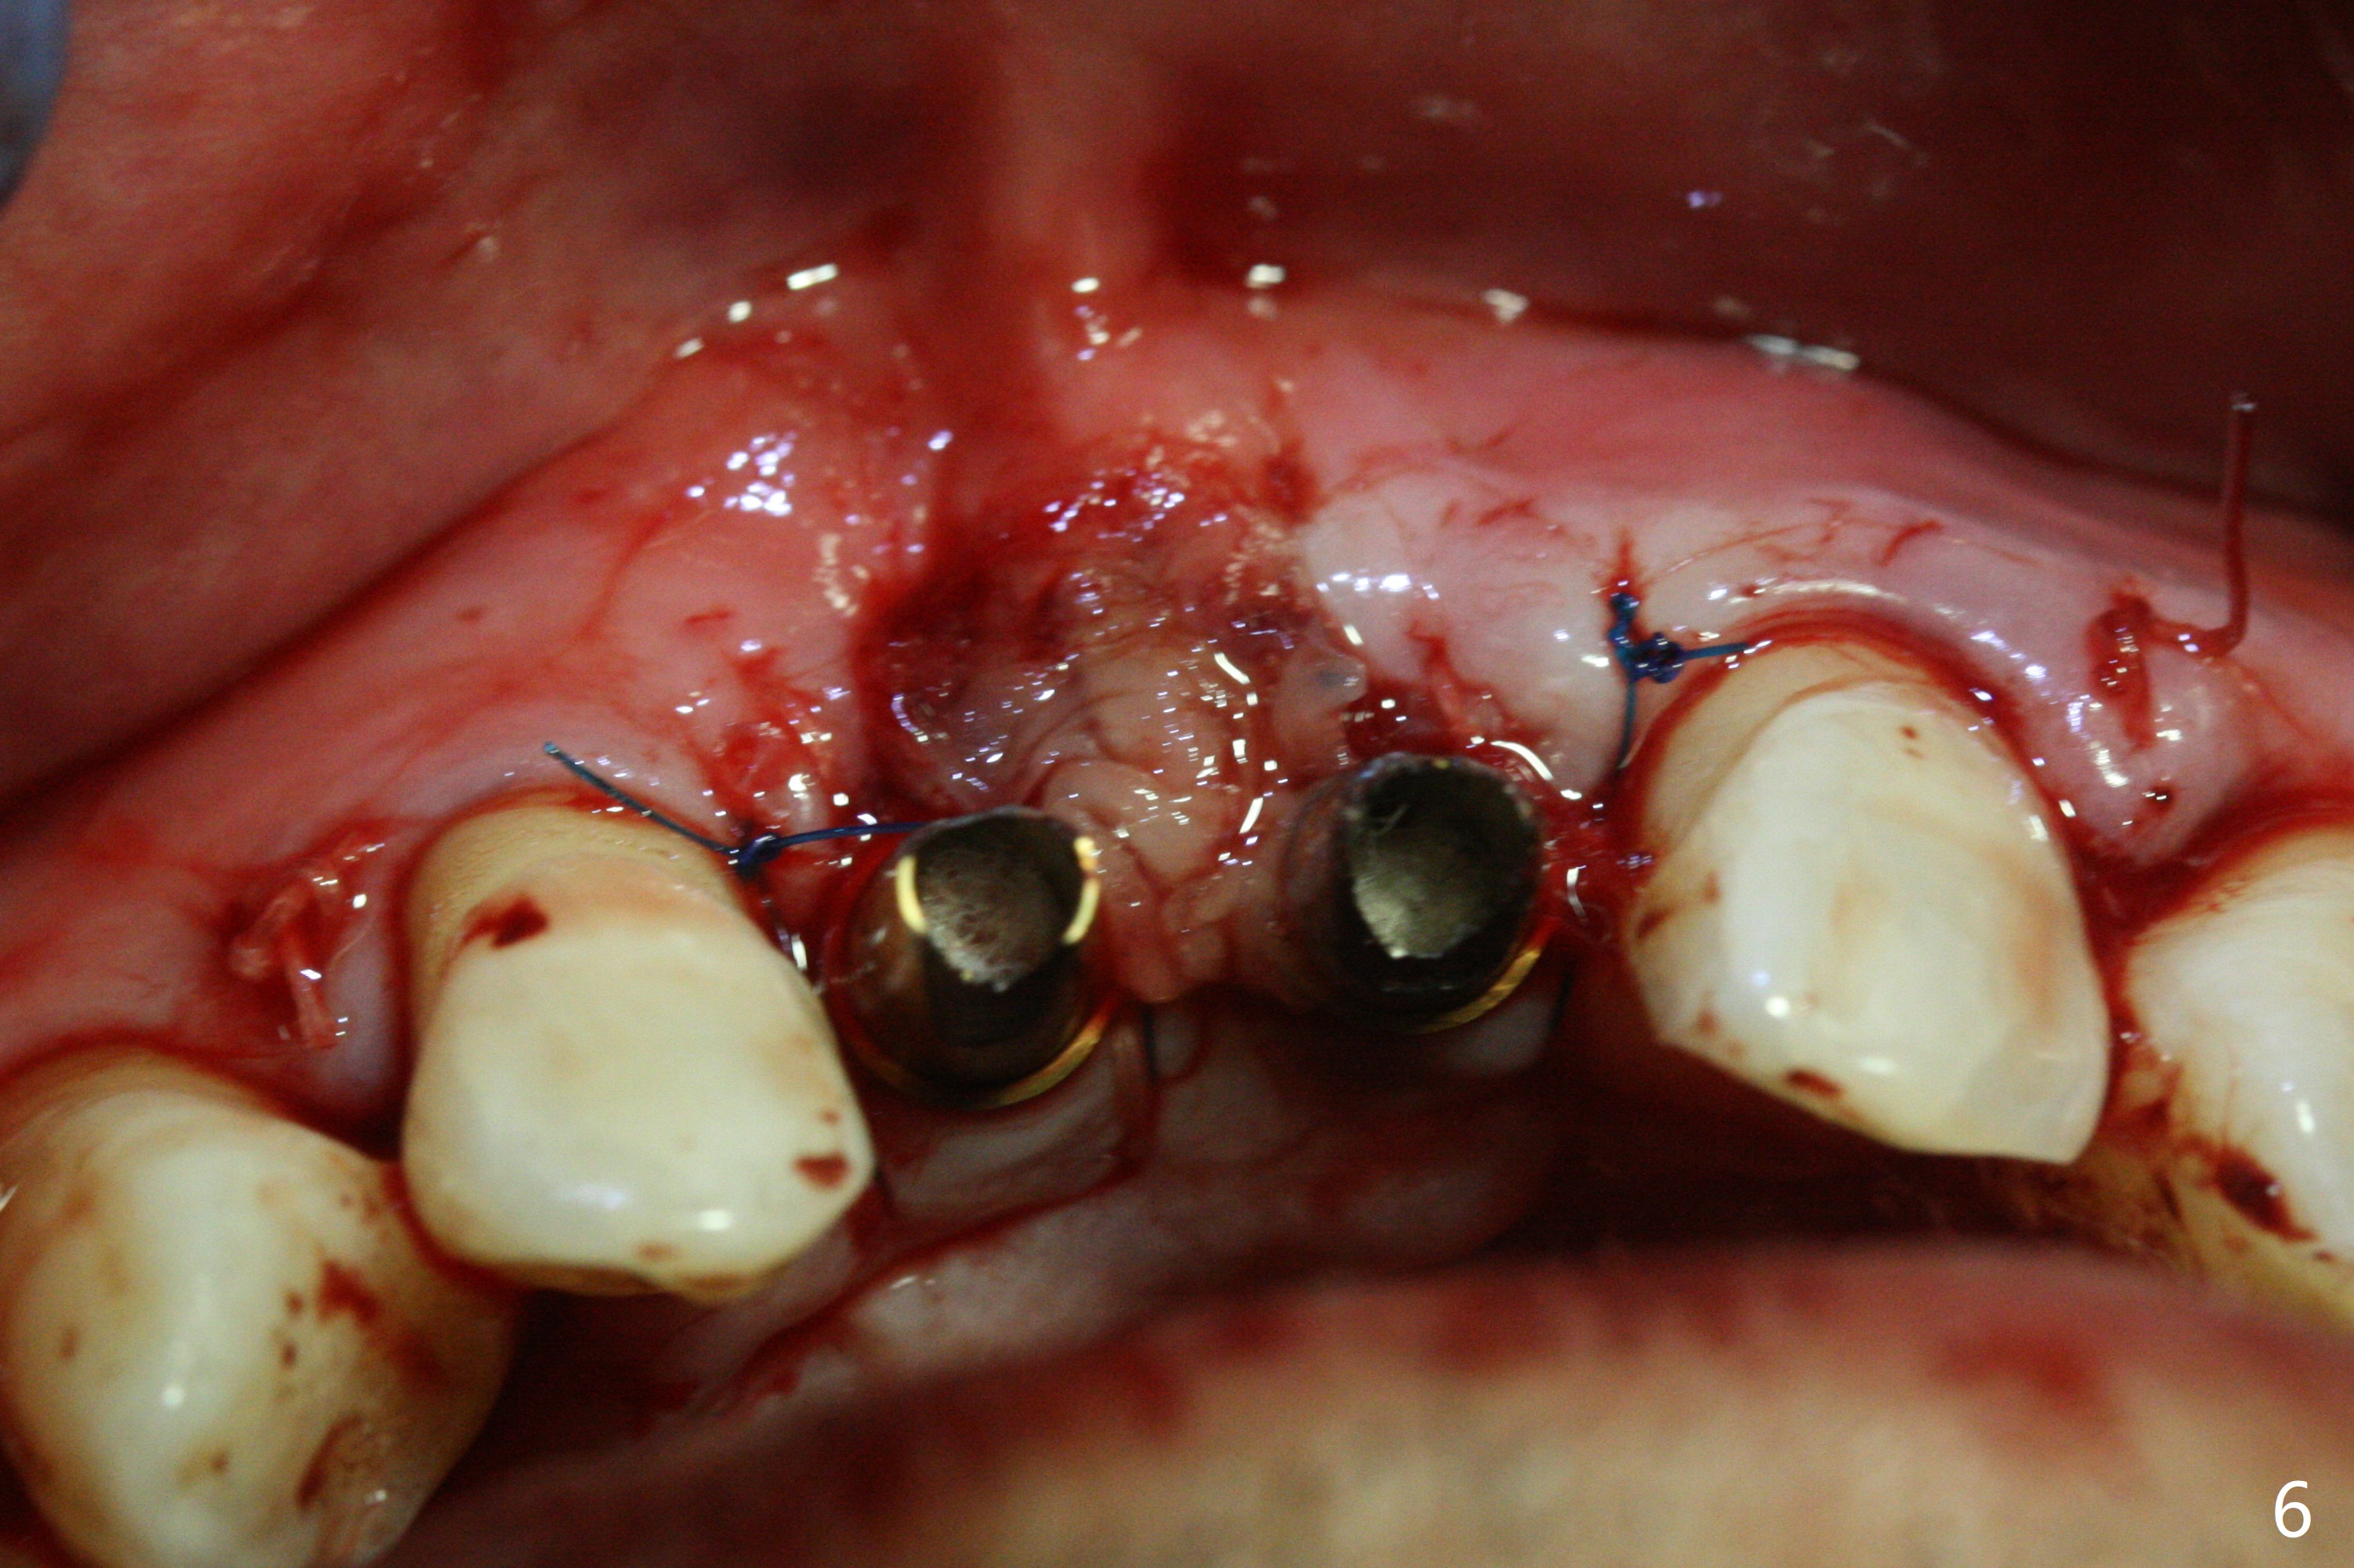

The gingiva remains recessive at #8 and 9 six months post immediate implant placement with bone graft (Fig.1). The buccal plate at #8 is particularly concave before (Fig.2 *) and after (Fig.3) abutment removal. The bony defect repair is assisted by placing a 4 mm tenting screw between the 2 implants (Fig.4) and placing allograft mixed with PRF (as putty) around the screw (Fig.5 (after replacement of the abutments)). The buccal contour improves because of the tenting screw and the bone graft placement (Fig.6 (as well as PRF and 6-month membranes)). The wound dehisces 12 days postop and immediately before leaving country for months (Fig.7). The sutures are removed, Osteogen plug is inserted (Fig.8) and periodontal dressing is applied (Fig.9). PA is taken to show the tenting screw (Fig.10 T). The latter is exposed 3 months postop (Fig.11,12). It appears that gingival graft is a must (Fig.13). Make a palatal stent, remove the temp with abutments and create a bleeding surface before harvesting a large piece of tissue. Connective tissue graft is done 5 months post bone graft (Fig.14). In fact there is no implant thread exposure. In fact the connective tissue graft does not survive. The abutments are re-prepared for pink porcelain (Fig.15). The bone loss is stable 1 year post cementation in spite of incomplete abutment seating (Fig.16). The soft tissue is nearly normal (Fig.17).